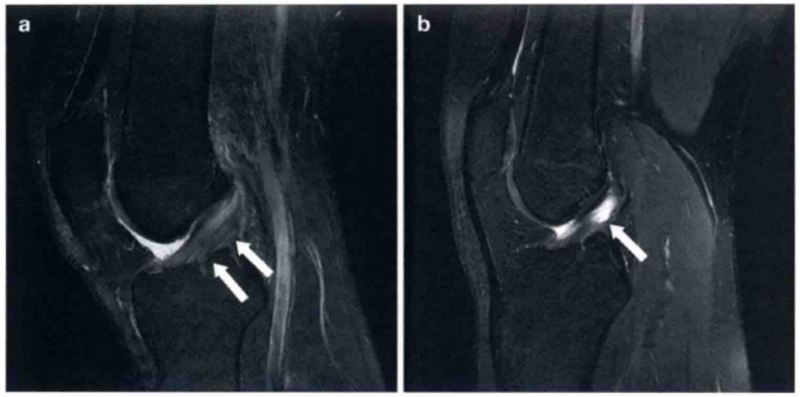

正常PCL的形态完全不同于ACL。在所有的MRI序列上,PCL均呈现同样的低信号,而且在实质部均有一个折弯(图8)。与ACL不同,PCL损伤通常较轻微,完全的PCL断裂较少见。不管是完全断裂还是部分断裂,在矢状位片上PCL成像均较清楚。PCL部分断裂常常表现为韧带变粗,实质内可见高信号(图9)。此外,当MRI检查发现有ACL和PCL损伤时,应仔细检查后内侧复合体、后外侧复合体以及半月板是否有外伤。

图8 a和b显示在T2和质子加权像上为正常的PCL,可见正常的弧度和在两个序列中为均值低信号

图9 a和b显示的为矢状位质子加权像和T2上PCL损伤的图像(箭头)。PCL变厚、水肿,但不是完全的断裂